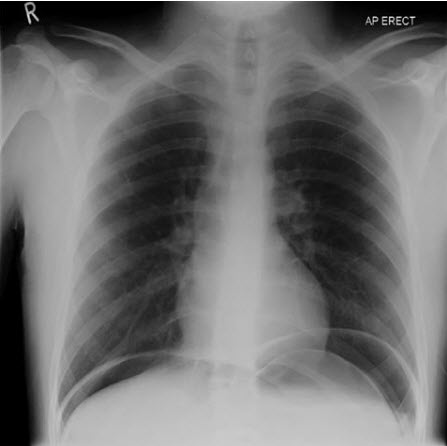

Bệnh nhân cần hồi sức tích cực, kháng sinh và chuyển phẫu thuật ngay lập tức. Khí tự do dưới cơ hoành trên Xquang ngực thẳng (có mặt ở 50- 70% trường hợp) sẽ xác nhận chẩn đoán; nếu Xquang ngực không chẩn đoán được, xem xét CT có thuốc cản quang. Amylase huyết tương có thể giúp phân biệt thủng tạng với viêm tụy cấp. Cần nghi ngờ cao ở những bệnh nhân lớn tuổi và dùng steroid toàn thân; những triệu chứng thường khó phát hiện nên cần đánh giá lại thường xuyên.

Hình. Khí tự do dưới cơ hoành